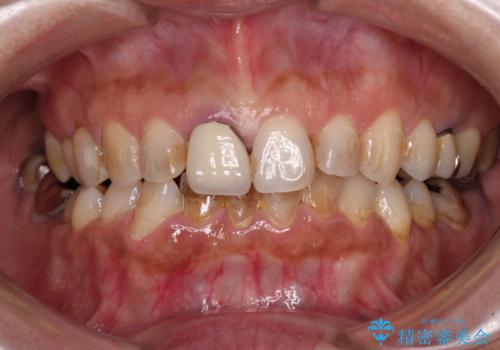

- 上下前歯のデコボコと、治療途中の歯を気にして来院された患者様です。

ご家族がインビザラインにて矯正治療を行っていたため、ご本人の希望によりインビザラインによるマウスピース矯正を行うこととしました。

根管治療が必要な歯は事前に処置を行った上で矯正治療を開始し、概ね歯列が整ったところでセラミッククラウンなどに置き換え、その後インビザラインを1セット使用して仕上げていくこととしました。